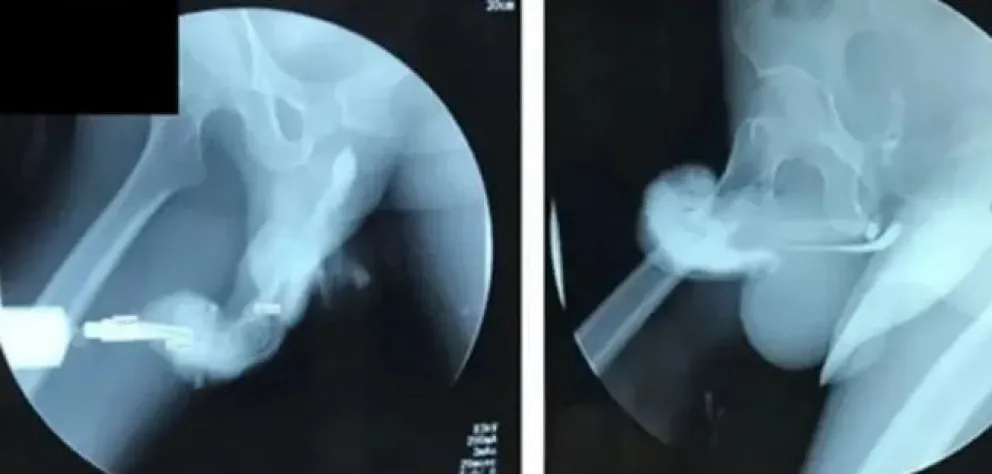

Su “miembro” había sufrido entonces una hinchazón y tenía un color muy oscuro, síntoma de que había sufrido una rotura. Los médicos, al revisarlo, confirmaron que se había producido un desgarro en la túnica albugínea, que es el tejido que permite que el miembro se agrande y se pueda poner erecto. Además, el hombre presentó un hematoma severo, lo que hizo que la sangre pasara al tejido circundante.

El diagnóstico es, según los especialistas, sencillo, debido a que los síntomas son evidentes por lo tanto fáciles de detectar. A este tipo de fracturas, en las que el pene se tuerce “debido a un traumatismo cerrado durante las relaciones sexuales”, se las conoce entre los médicos como “deformidad de la berenjena”.